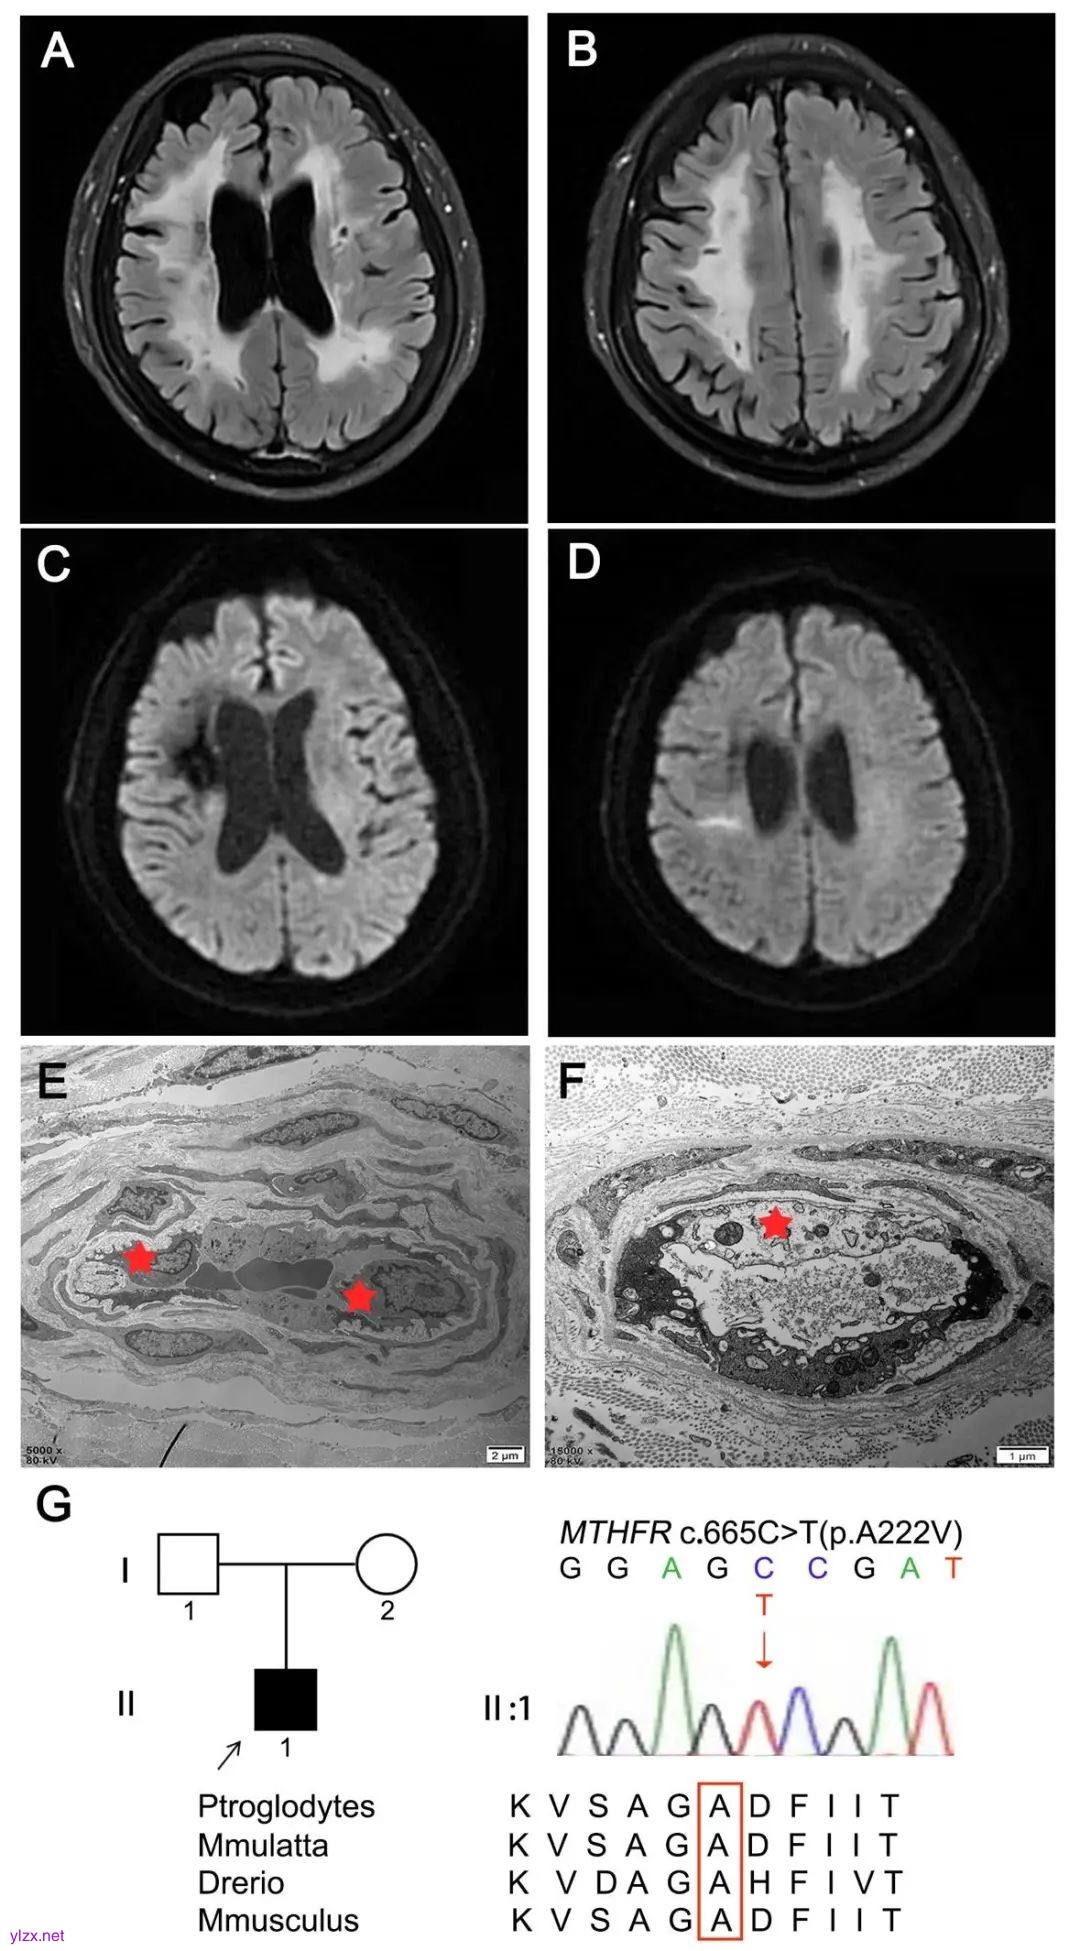

辅助检查:肾小球滤过率(estimated glomerular filtration rate epidemiology collaboration,eGFR-EPI) 43.48 mL/min(参考值90~120 mL/min),尿素6.8 mmol/L(参考值2.89~7.85 mmol/L),肌酐147.6 μmol/L(参考值53~106 μmol/L),尿酸448 μmol/L(参考值150~416 μmol/L),胱抑素-C 1.48 mg/L(参考值0.6~2.5 mg/L),D-二聚体0.83 mg/L(参考值0~0.5 mg/L),甘油三脂1.90 mmol/L(参考值0.45~1.69 mmol/L),低密度脂蛋白2.39 mmol/L(参考值2.07~3.10 mmol/L),糖化血红蛋白6.2%(参考值4.0%~6.0%)。下肢血管超声提示两下肢动脉硬化伴斑块形成,两下肢深静脉未见血栓。颈动脉血管超声提示双侧颈动脉硬化、右侧小斑块形成。头颅磁共振血管造影提示颅内动脉粥样硬化。头颅磁共振提示双侧对称弥漫性脑白质病变,Fazekas 3级(图1A、B),右侧顶枕叶、胼胝体左侧压部亚急性期脑梗死(图1C、D),双侧小脑、脑干、丘脑、基底节区多发散在腔梗灶、含铁血黄素沉积。周围神经电生理、肌电图基本正常。左足外踝上方皮肤活检,表皮内神经纤维密度(intraepidermal nerve fiber density,IENFD)提示皮肤小纤维神经密度正常,蛋白基因产物9.5(protein gene product 9.5,PGP9.5)染色IENFD 6.02根/mm(同年龄男性正常对照范围:2.4~6.3根/mm),生长关联蛋白43(growth associated protein,GAP43)染色IENFD 1.08根/mm(0.89~2.33根/mm)。表皮和真皮内个别血管周围炎细胞浸润,超微电镜提示真皮层内广泛小血管的内皮细胞肿胀(图1E)或胞质结构崩解(图1F),线粒体无明显异常,未见嗜锇颗粒沉积(图1E)。

Fig.1 The brain imaging features,electron microscopy of epidermal micro vessel, pedigree and Sanger sequence of the patient with hyperhomocysteinemia due to homozygousMTHFRmutation

图1MTHFR纯合变异所致高同型半胱氨酸血症:头颅磁共振、皮肤电镜、家系图及一代测序结果 A、B,双侧对称弥漫性脑白质病变,Fazekas 3级(T2-Flair相);C、D,右侧顶枕叶、胼胝体左侧压部亚急性期脑梗死(DWI相);E,皮肤超微电镜检查示真皮层内小血管内皮细胞肿胀(红星),血管平滑肌细胞结构正常,未见嗜锇颗粒沉积;F,皮肤超微电镜检查示血管内皮细胞胞质结构崩解(红星);G,该先证者(Ⅱ:1)存在MTHFRc.665C>T纯合变异,该位点在多个物种间高度保守。

遗传学检查:抽取患者肘静脉外周血,进行全外显子组测序(whole exome sequencing,WES),结果显示MTHFR基因纯合致病性变异c.665C>T(p.A222V)(图1G)。该变异为已知致病性变异,根据美国医学遗传学与基因组学学会(American College of Medical Genetics and Genomics,ACMG)评估和分级指南[7],该变异被评为“致病”(PS3+PS4+PM3+PP3)。予维生素B12(0.25 mg/d)肌肉注射、维生素B6(每天3次,每次20 mg)口服、甜菜碱(1.5 g/d)口服,1个月后Hcy显著降低至20.50 μmol/L,配合脑梗后康复训练,运动和语言较前好转。